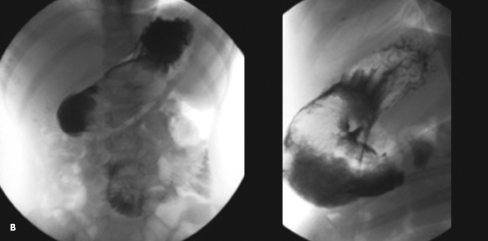

Poonam Mahajan, MD; La Donna J. Johnson, MD

For the second time in a week, a 6-year-old girl was brought to the hospital with poorly localized epigastric and periumbilical pain. The pain was crampy and when severe, the child would yell.